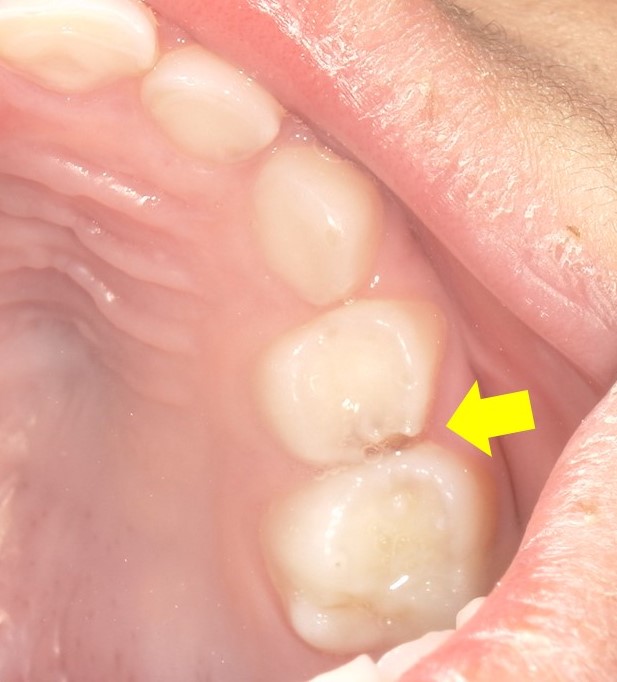

そんなお子さんに特徴的なのは虫歯の部位です。大半は奥歯の歯と歯の隙間に虫歯ができてくるケースが非常に多いのです。

なぜならお口の汚れは奥歯と奥歯の隙間にも停滞するからです。

歯と歯の間の汚れはフロスを通さないと完全に取れませんし、もともと子供の歯は大人よりも隙間が開いていることが多いので、どうしても汚れが停滞しやすく、磨き切れていなく、虫歯になってしまいやすいのです。